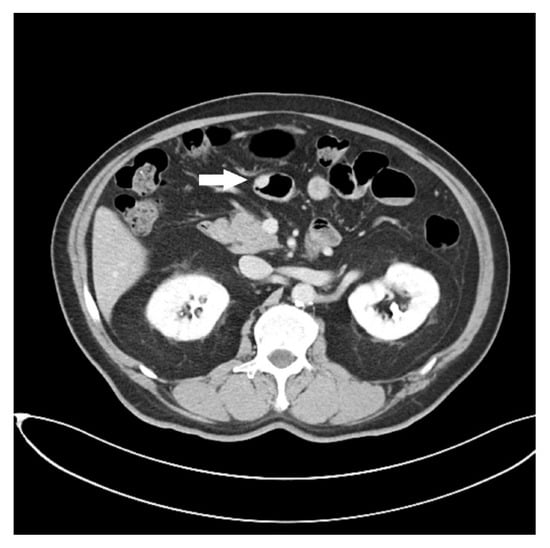

Endoscopic Ultrasound Appearance of Jejunal Ectopic Pancreas Mimicking Metastatic Nodule in a Cancer Patient

Lee, C.-W.; Lin, Y.-C.; Hsu, H.-T.; Chen, Y.-Y.; Yen, H.-H. Endoscopic Ultrasound Appearance of Jejunal Ectopic Pancreas Mimicking Metastatic Nodule in a Cancer Patient. Diagnostics 2023, 13, 660. https://doi.org/10.3390/diagnostics13040660